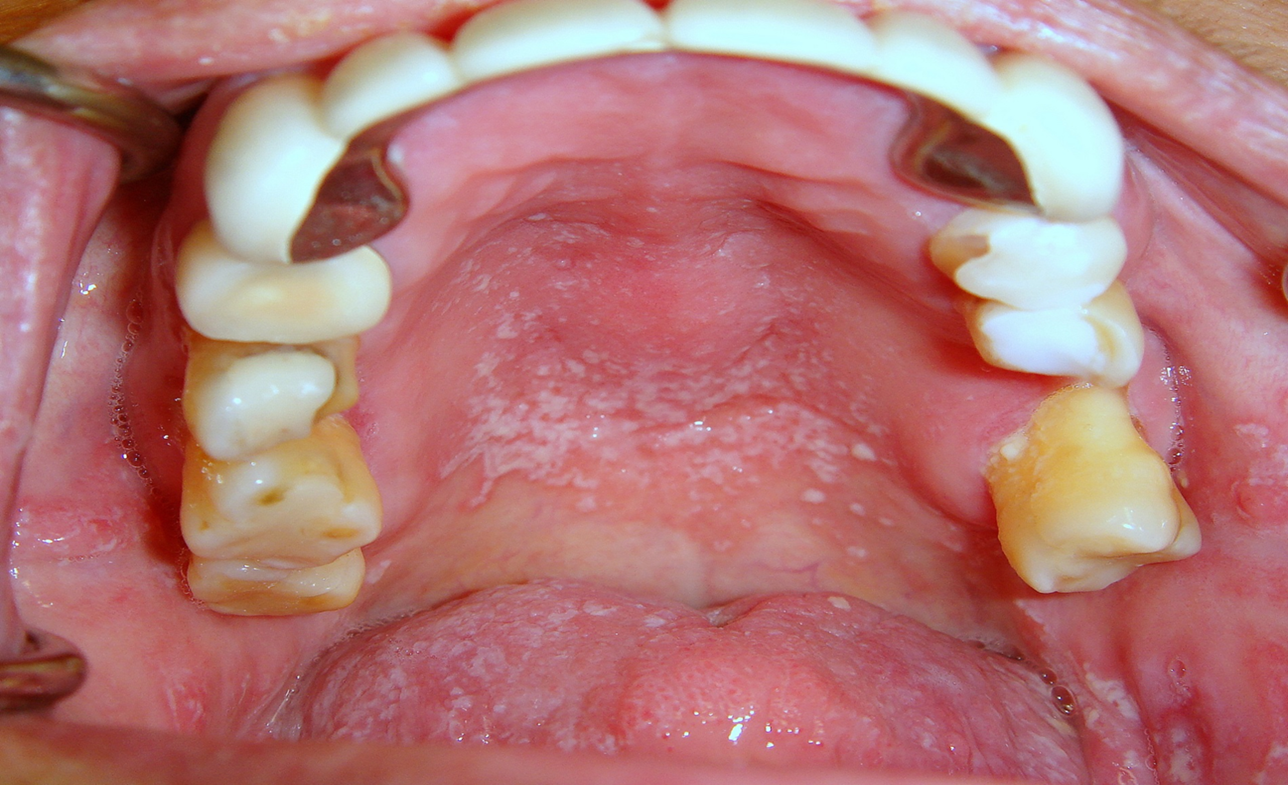

Dental caries, both new and recurrent, is also a frequently occurring infection resulting from lack of saliva. Older adults are particularly vulnerable because many have a greater number of retained natural teeth, previously restored dental surfaces, and gingival recession.11 Recurrent carious lesions are seen particularly in the buccal surfaces of previously restored anterior teeth and in incisal margins4 (Figure 1). Without proper salivary flow to restore the oral pH levels and to regulate bacterial populations, the oral cavity is rapidly colonized with caries-associated microorganisms.11 In regard to periodontal disease, the evidence in the literature is conflicting as to whether individuals with xerostomia are at an increased risk for periodontal disease. Some studies26-31 showed that the periodontal condition of individuals with Sjögren’s syndrome is similar to control individuals, whereas others demonstrated that these patients may have a worse periodontal condition compared to controls.32-34 These studies attributed the poorer periodontal conditions observed in individuals with xerostomia to the decrease in the amount of saliva and, consequently, the increase in plaque.35

Fig 1. Patient with rampant buccal/cervical caries due to long-term use of anticholinergic drugs.

Figure 1